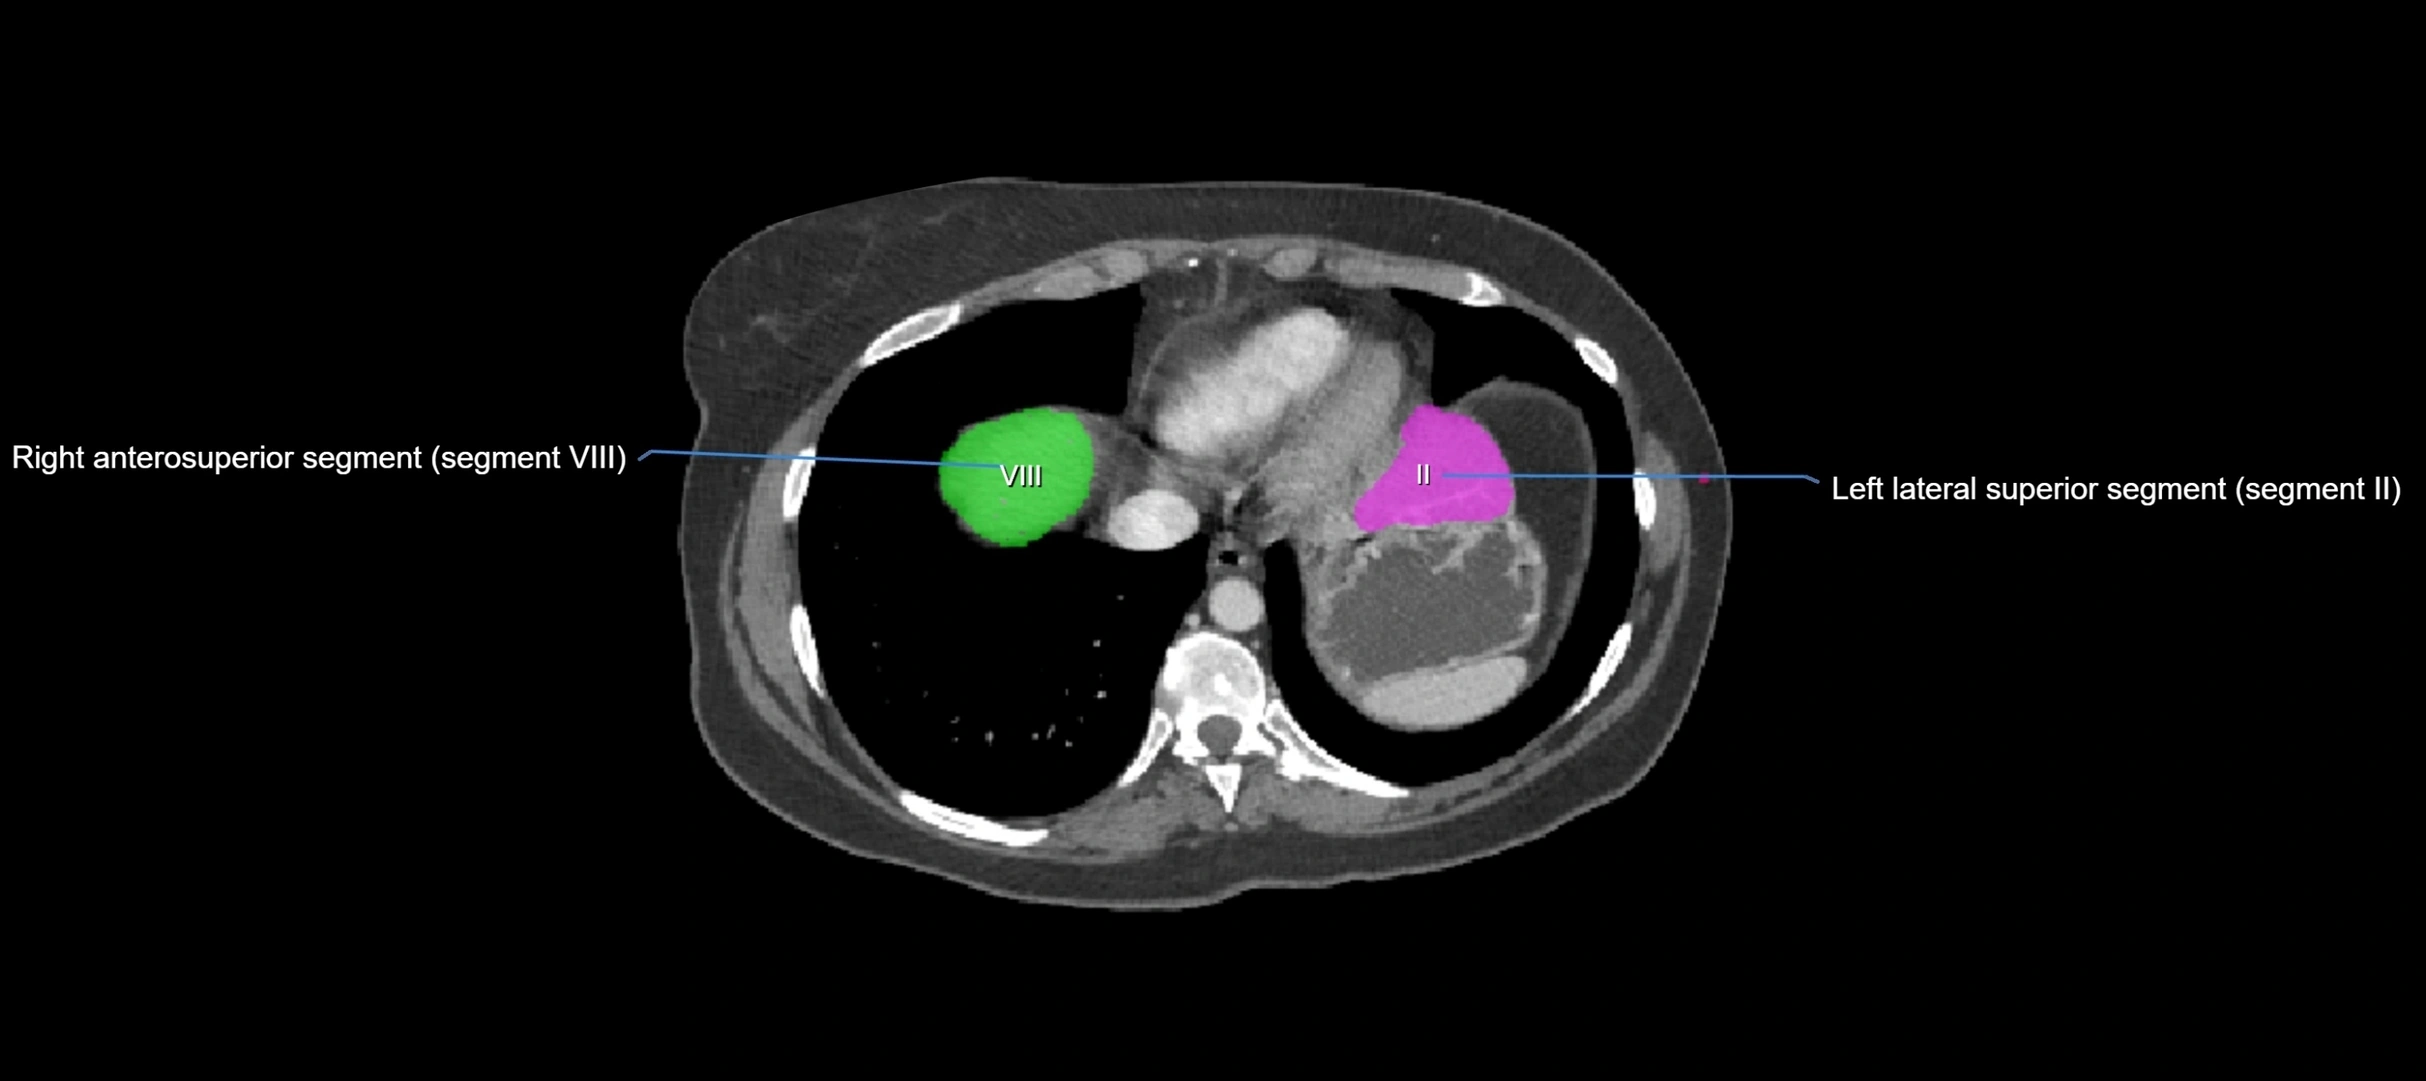

CT Image

image